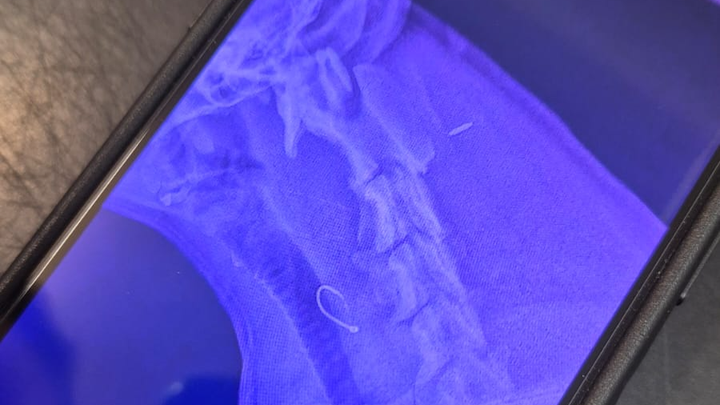

My name is Michelle I'm raising funds for Lissy Harris she swallowed a fishing hook today and is currently in surgery the vets are trying to remove the hook but are struggling to locate it.